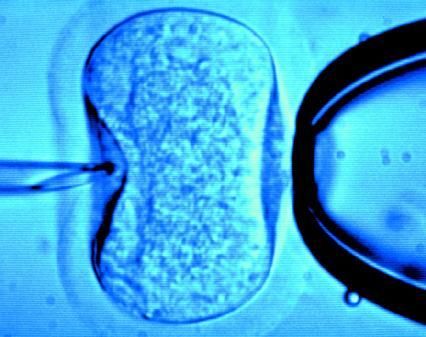

據(jù)英國《每日郵報》1月18日報道,英國一位60歲老婦將成為英國接受試管受精最年長者。這位老婦名叫蘇珊·托勒夫森,是一位退休教師,到今年10月她就滿60歲了。2008年,蘇珊曾去俄羅斯接受試管受精,在英國生下了她的第一個孩子。

倫敦哈利街的私人診所是英國試管嬰兒手術(shù)成功率較高的醫(yī)院之一,醫(yī)生們在上周一同意幫助蘇珊·托勒夫森進(jìn)行第二次人工受孕。通常情況下,私人診所只在特殊情況下給50歲以上的婦女進(jìn)行試管受精,例如,患者仍然有月經(jīng)周期。這件事引起了絕經(jīng)后婦女是否有生育權(quán)利的倫理大討論,現(xiàn)在要求提高生育治療年齡上限的呼聲越來越高。

現(xiàn)在,蘇珊·托勒夫森一家人很幸福,丈夫尼克·邁耶是一位公司經(jīng)理,比她小11歲,他們的女兒今年2歲。專家表示,蘇珊很健康,她的女兒如果能有一個兄弟姐妹會更好,于是蘇珊想再次接受試管受精!缎瞧谌锗]報》獲悉,倫敦哈利街私人婦女診所的高級工作人員已經(jīng)同意為蘇珊做試管受精,還決定幫助另一位57歲的老婦受孕。(海瀾)